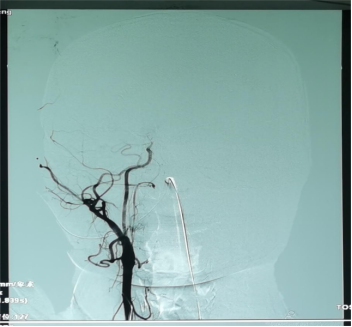

患者脑血管造影